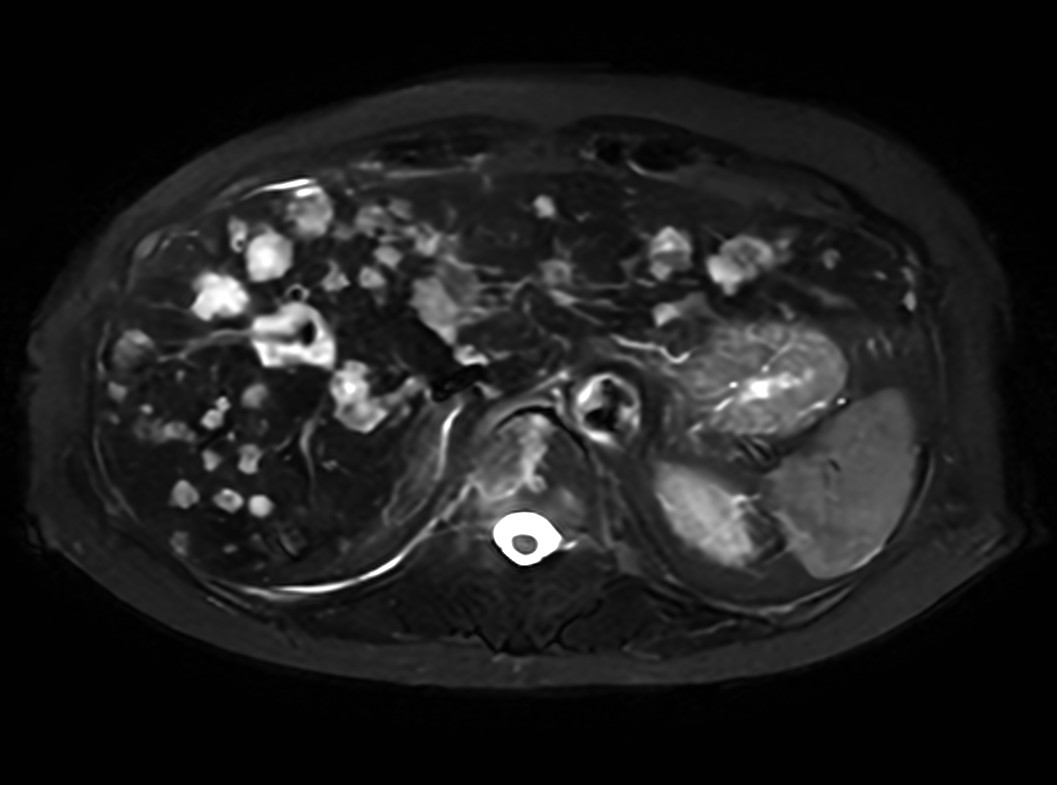

Axial T2w SSh

Axial Heavy T2w SSh FatSat